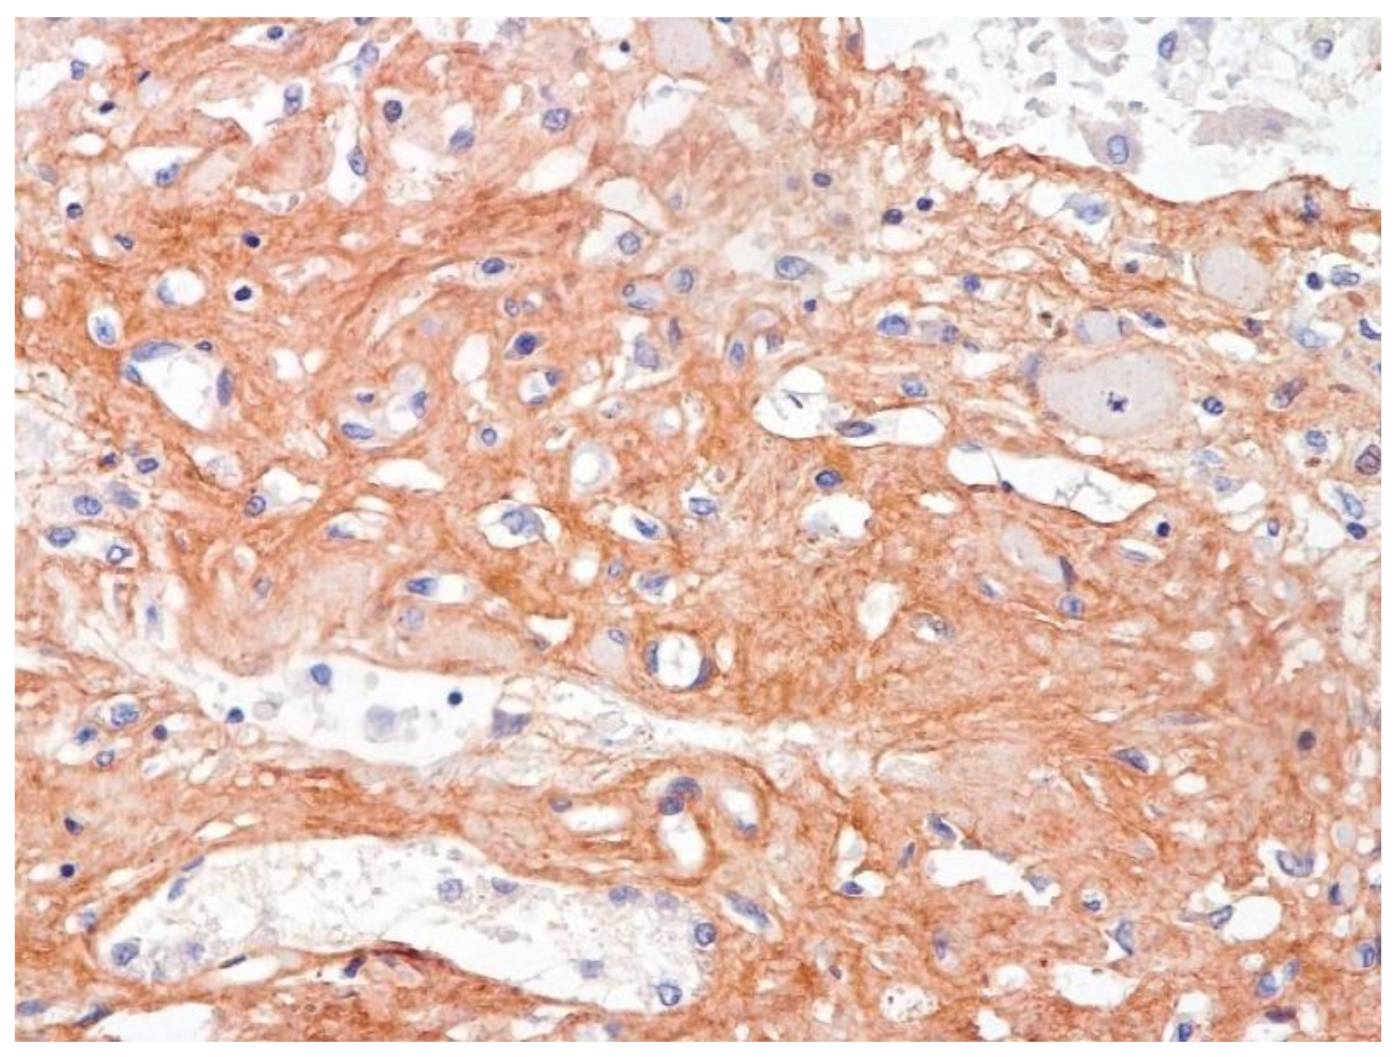

The dynamics of changes in ARDS associated with COVID-19 can only be judged by analogy with SARS and influenza A/H1N1pdm. In the late (productive) stage (after 7–8 days or more from the onset of the disease) of diffuse alveolar damage, macroscopically the lungs are enlarged, low-air, dense, fleshy, and can resemble the density of the liver, sometimes with diffuse whitish layers and areas of different sizes. Microscopically, siderophages, a relatively (in comparison with swine influenza) small number of hyaline membranes (Figure 9), fibrin, squamous metaplasia of the bronchial, and bronchiolar and alveolar epithelium can be detected in the lumens of the alveoli, respiratory and terminal bronchioles, the thickening of the interalveolar septa due to sclerosis, lymphoid (mostly CD3+ and CD 8+) (Figure 10 and Figure 11) and macrophage (Figure 12) infiltration, and the proliferation of type II alveolocytes. The nature of cytoproliferative changes of the epithelium in the trachea and bronchi remains unclear. In the final stage of the disease, sections of fibrous tissue may develop in all parts of the lungs (usually in the lower lobes) (Figure 13), which contributes to the development of chronic respiratory failure. It is notable that near the overgrowth of collagen fibers in the lungs, neoangiogenesis is also typical (Figure 14). The electron microscopic study revealed changed viral particles (Figure 15).

Figure 13.

Fibrosis in lung due to collagen 3. IHC ×200.

Figure 14.

Neoangiogenesis in lung by CD34+ cells. IHC ×200.